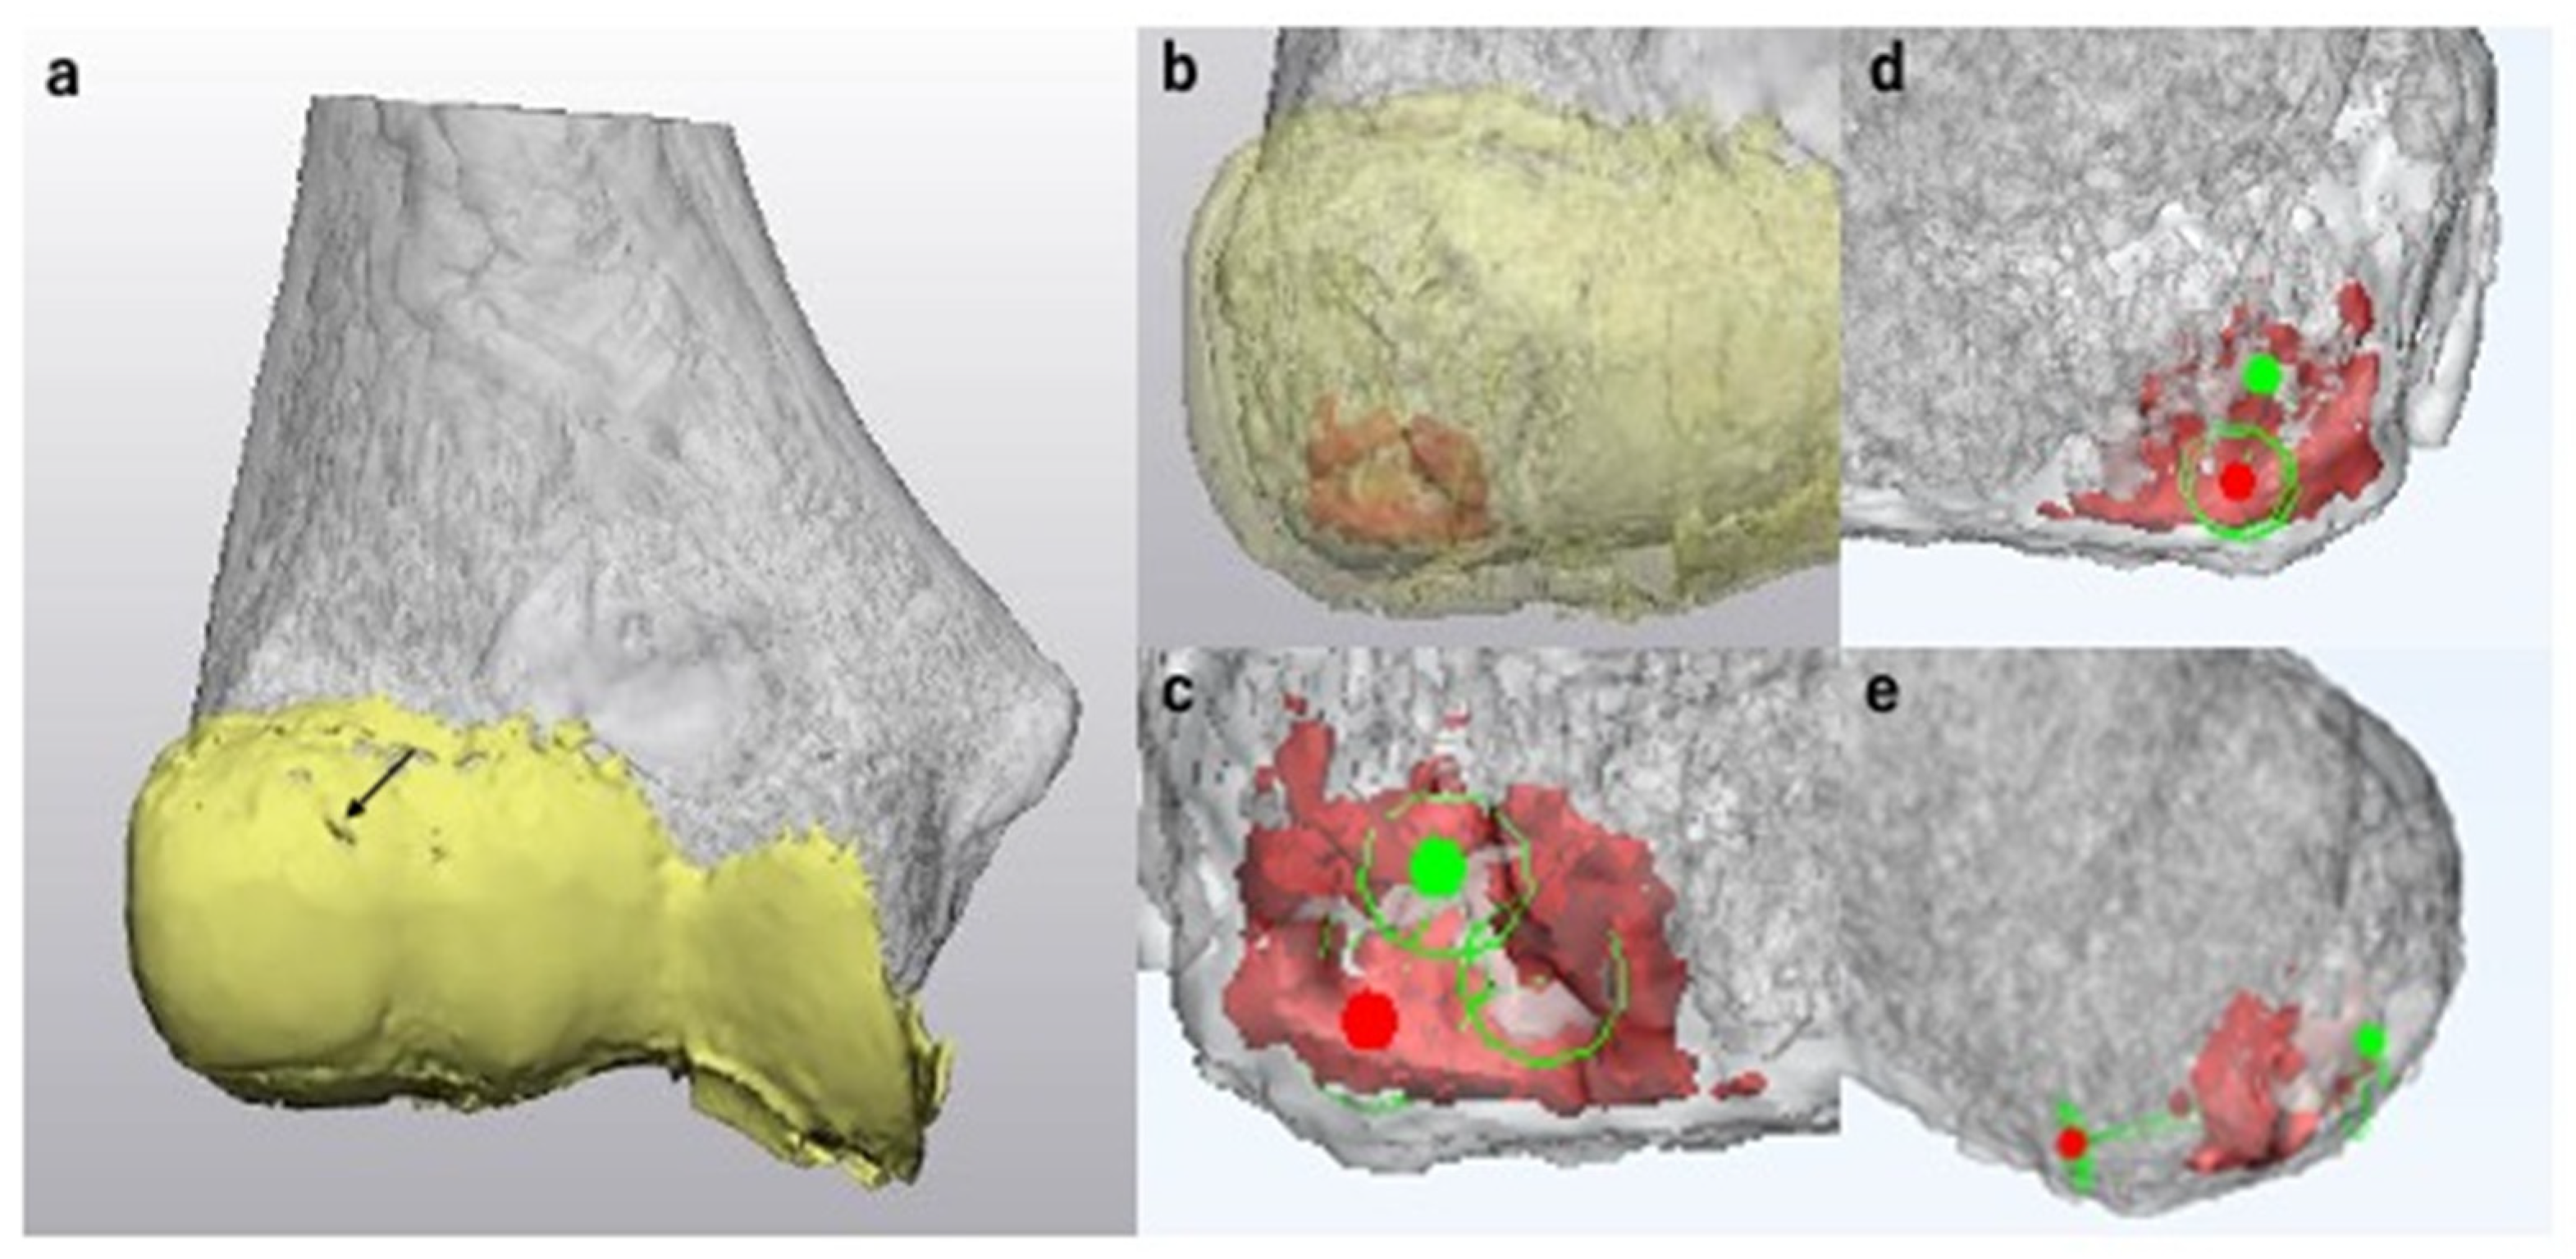

2.5. Lesion Evaluation Using MCFIs

2.6. Surgical Simulation

3.1. Lesion Evaluation Using MCFIs

3.3. Surgical Simulation